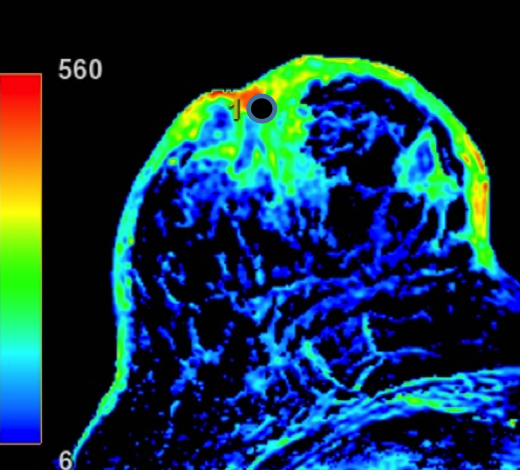

2. Describe los hallazgos por RM:

- C. Engrosamiento cutáneo en CCII de MD con realce heterogéneo nodular asociado a un realce tipo no masa retroareolar con curvas funcionales sospechosas (tipo 2).